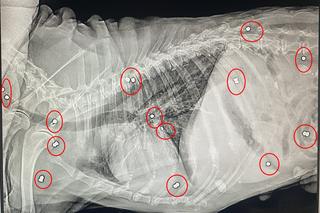

„Pomimo wielu lat działań i ogromu przeprowadzonych interwencji jeszcze NIGDY nie widzieliśmy tak podziurawionego śrutami zwierzęcia” – piszą przedstawiciele lubelskiej Fundacji na Rzecz Ochrony Praw Zwierząt Ex Lege. Bagier, bo takie imię nosi pies, którego aktywiści odebrali właścicielowi, stanowił żywą tarczę strzelniczą.

Bagier to starszy psiak w typie beagle’a, który doznał już mnóstwo cierpienia. Fundacja Ex Lege przyznaje, że wyniki badań diagnostycznych, jakie przeszedł, zszokowały także weterynarzy. W ciele psa odnaleziono bowiem wiele metalicznych śrutów, które znajdowały się na jego brzuchu, klatce piersiowej oraz szyi. Bagier był także bardzo zaniedbany – ma liczne wyłysienia, a w sierści pełno pcheł. Dokucza mu także świąd, a do tego psiak jest niesłyszący i kuleje, często ma też duszności i kaszle.